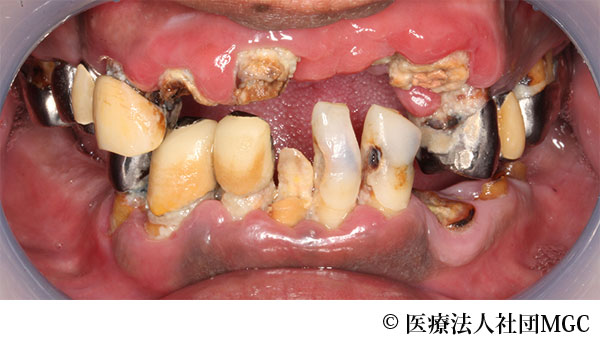

【症例1】上下All-on-4(オールオンフォー)

- 治療前

患者様の症状

歯がボロボロで食事が困難であるとご来院されました。

治療法

ご相談の結果、患者様の生活の質(QOL)を向上させ、しっかり噛めるように上下All-on-4(オールオンフォー)を行いました。

治療結果

機能性、審美性ともに改善し、満足していただけました。